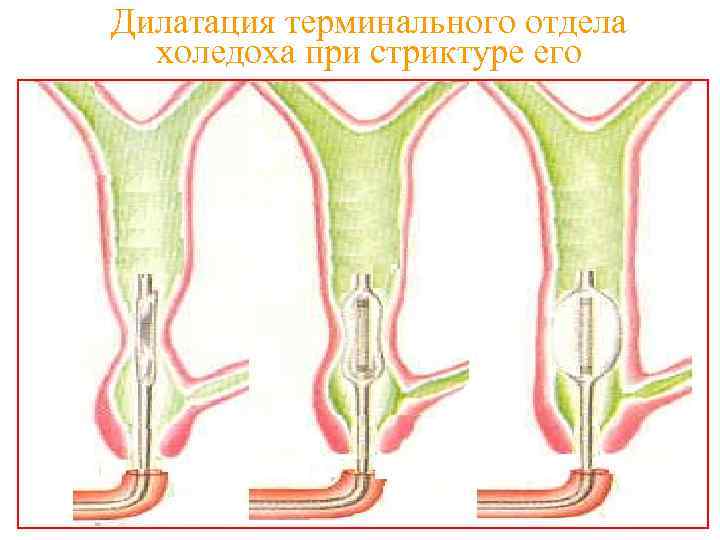

Дилатация терминального отдела холедоха при стриктуре его